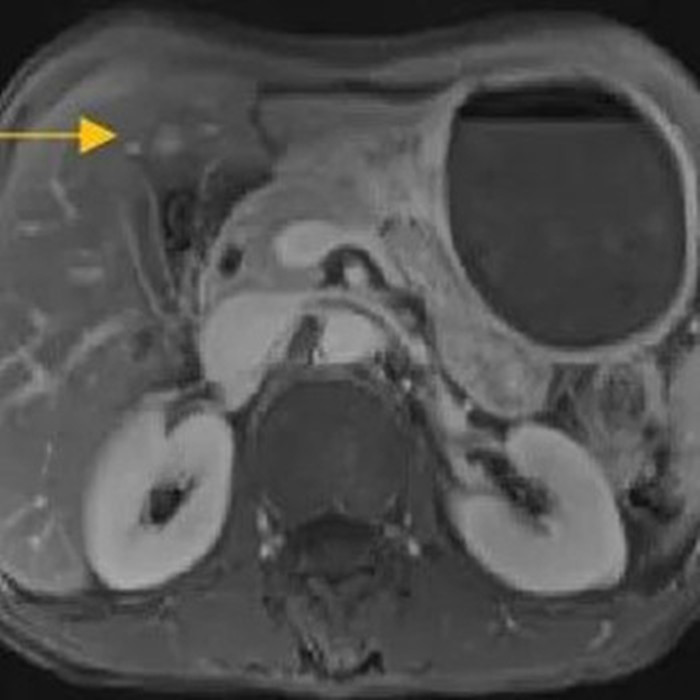

住院后經(jīng)胸腹部CT檢查,提示周先生胃部巨大腫塊穿破胃腔,可能累及到結(jié)腸,同時(shí)合并有胃旁淋巴結(jié)轉(zhuǎn)移、肝臟的轉(zhuǎn)移??吹竭@個(gè)檢查報(bào)告后,周先生和他的愛(ài)人一下子就泣不成聲了。

治療前的腹部CT提示胃

經(jīng)過(guò)6個(gè)周期,前后4個(gè)月的治療,周先生再次復(fù)查CT,提示胃部腫瘤,轉(zhuǎn)移的胃旁淋巴結(jié)、肝臟腫瘤都有明顯縮小,營(yíng)養(yǎng)狀況良好,能正常進(jìn)食,體重增加了6斤,精神狀態(tài)比原先好了很多。

治療前

治療后